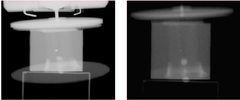

(a)

본 연구에 사용되는 선형가속기 장비는 iX(Varian, US)[ Fig. 4]로 방사선 치료에 사용되는 Mega-Voltage 강도의 X선을 사용하여 EPID를 통해 radiography를 촬 영 할 수 있다. 또한 치료용 방사선을 발생시키는 gantry 와는 수직으로 위치하여 beam이 교차하는 구조적 위치 에 장착 된 OBI를 이용하여 kilo-voltage 강도의 X선으 로 single shot radiography, 투시촬영 및 CBCT 영상을 진단용 CT 장치에서는 BB 팬텀이 움직이지 않는 상 태의 기준 영상과 구동팬텀을 함께 사용하여 4초주기로 움직이는 상태의 두 가지 시리즈로 CT 촬영을 실시하였 다. 선형가속기에서는 3차원 구동팬텀과 BB 팬텀을 함 께 사용하여 호흡주기 4초의 구동 팬텀에 대하여 gating 을 적용하지 않은 kV-CBCT, gating을 적용한 kV-CBCT와 mega-voltage CBCT(MV-CBCT)를 촬영

상태에서 영상을 획득한다. 즉, 특정 호흡 순간의 영상을 얻지 못한다. 따라서 본 연구에서는 RPM을 이용한 gating 기술을 적용하며 OBI와 EPID를 이용해 각각의 back projection 영상을 획득 하였다[Fig. 5]. 조사면은 10×10cm, gantry는 0 ~ 180°까지 1°간격으로 회전하면 서 back projection 영상을 획득하였다. 이렇게 획득한 back projection 영상들을 Matlab(MathWorks, US)을 이 용하여 filtered back projection 알고리즘으로 각각의 CBCT영상으로 단면영상을 재구성하였다.

(a) sample image using OBI with kV-CBCT (b) sample image using EPID with MV-CBCT